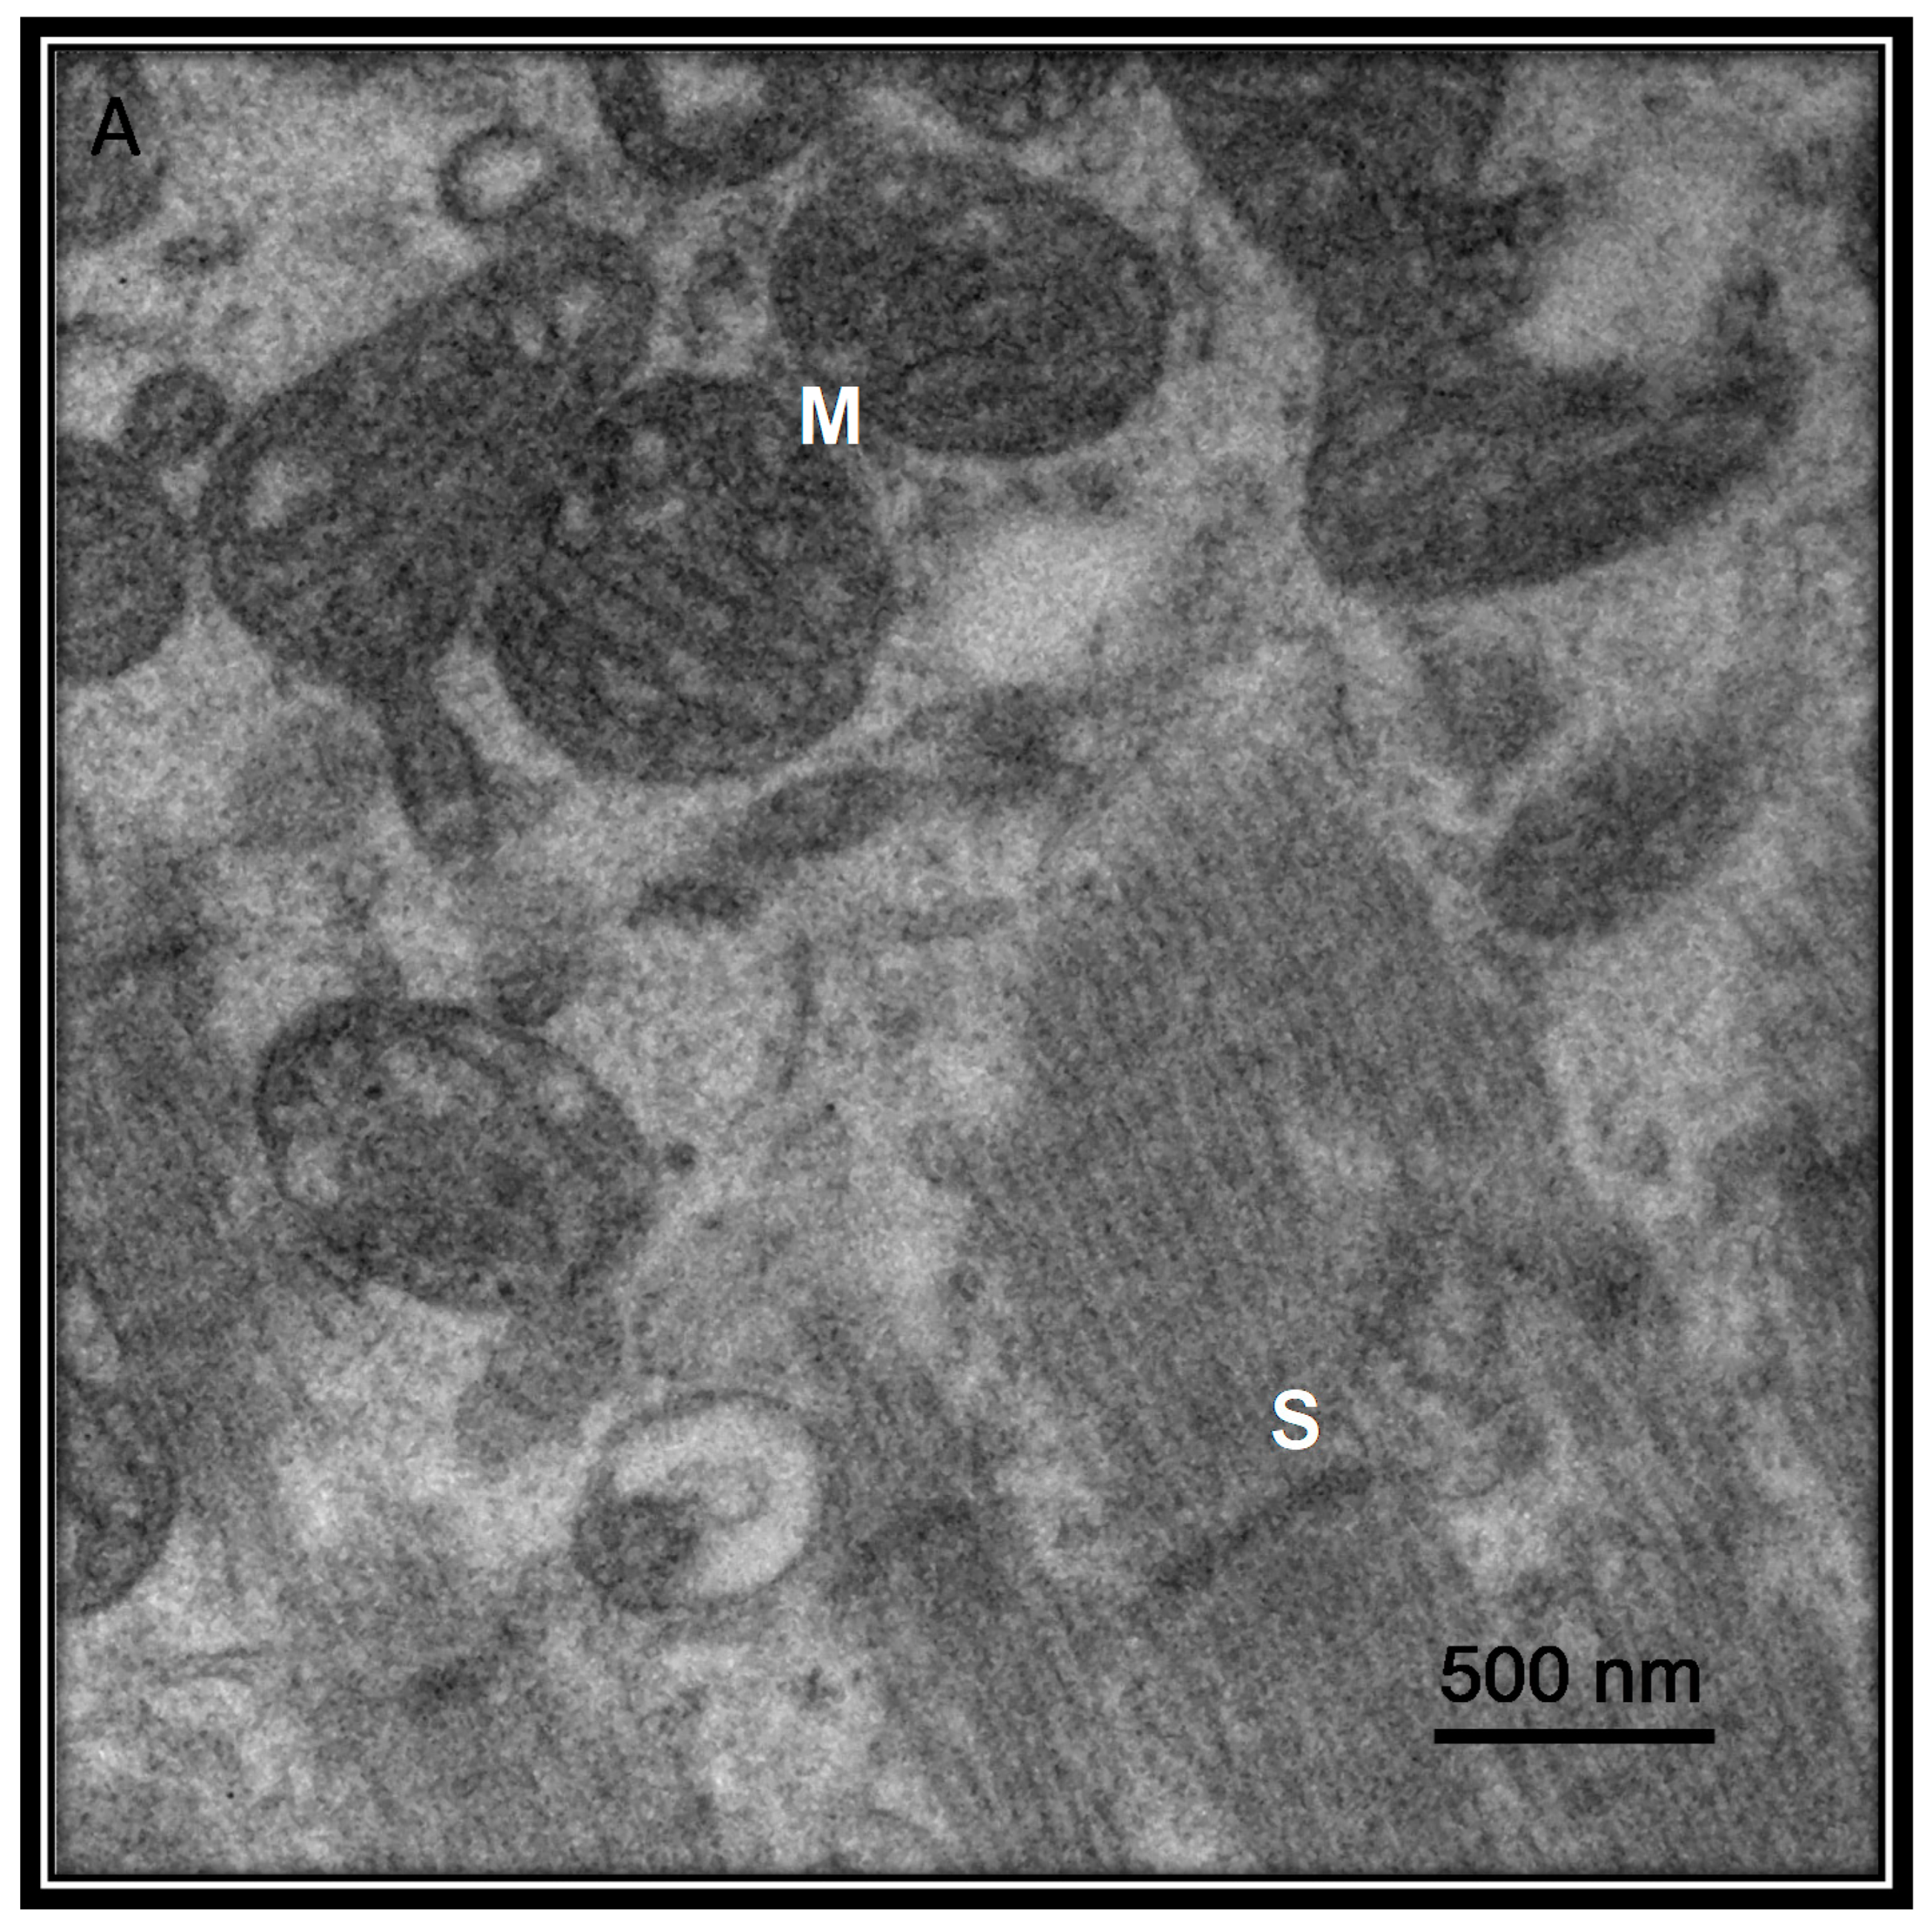

- Qu, C.; Zhang, S.; Li, Y.; Wang, Y.; Peppelenbosch, M.P.; Pan, Q. Mitochondria in the biology, pathogenesis and treatment of hepatitis virus infections. Rev. Med. Virol. 2019, 29, 2075. [Google Scholar] [CrossRef]